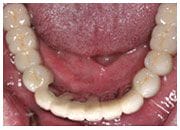

下顎治療

治療前

治療後